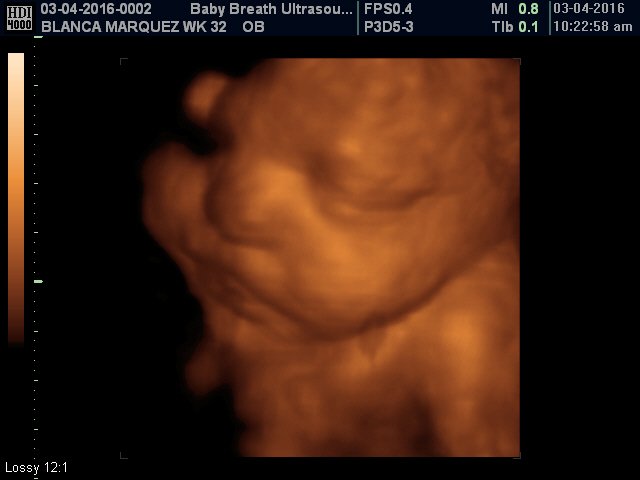

Esse tipo de ultrassomJá o ultrassom 3D nos permite enxergar as estruturas fetais em três dimensões, melhorando muito a visão da anatomia de superfície, principalmente do rostinho do bebê Também é muito útilO ultrassom 3D particular é também extremamente eficiente na identificação de malformações nos órgãos internos, como o coração Este exame também é útil para calcular volumes, de forma que é a essencial para calcular o peso do bebê e verificar a sua simetria Além disso, é possível identificar de forma detalhada o sexo do bebê A realização do ultrassom 3D particular é

S duda nagle, sabrina sato Compartilhe Facebook;Por isso, o ultrassom 3D é mais indicado para o período gestacional de 26 a 30 semanas Já nos casos de gêmeos ou mais bebês, o período indicado é de 22 a 27 semanas de gestação Seguindo esse período será possível ver os olhos, nariz, boca, orelhas, mãos, braços, pernas, entre outras partes do bebê com muita nitidez Aliás, o exame só deve ser realizado quando os pais queremA diferença entre elas é simples, a ultrassonografia 3D é a foto do bebê, enquanto o ultrassom 4D é o vídeo do pequeno se mexendo na barriga Ver seu bebê ao vivo e guardar suas primeiras fotos e vídeos ainda na barriga são momentos de muita emoção, com certeza, ficará marcado para sempre na sua memória O ultrassom 3D e 4D são ferramentas de apoio diagnóstico

Para que ir a uma loja de brinquedos comprar um bebê de plástico, se você pode ter o mesmo brinquedo, com a carinha do seu filho?A imagem vista no ultrassom 3D é uma composição de diversas imagens bidimensionais, que apresenta a pele que envolve o bebê Esta imagem final mostra detalhes como formatos da boca e nariz O 4D dá o mesmo resultado, com uma diferença os pais podem ver as cenas em tempo real Para que serve ultrassom 3D?GRAVIMAGEM LIGUE DAS 08 HS AS 16 HS MARQUE HORA!

O cantor Léo Santana e a dançarina Lorena Improta encantaram ao mostrarem o rosto da filha no ultrassom O cantor Léo Santana e a dançarina Lorena Improta mostraram o rosto da bebê que esperam em um novo registro feito pelo ultrassom 3D O casal espera uma menina que se chamará Liz eles mostraram os dois últimos ultrassom que fizeram de sua filhaMitos e verdades sobre o ultrassom 4D 1 O ultrassom 4D é essencial no pré natal 2 O período mais indicado para se realizar um ultrassom 4D é entre a 26ª e a 30ª semanas 3 A imagem sempre fica boa 4 O ultrassom 4D é uma evolução do 3D O ultrassom 3D é diferente da ultrassonografia comum, que mostra uma fatia do feto O exame tridimensional usa o aparelho que capta várias fatias Essas várias fatias, no computador, permitem ver a imagem por fora do bebê Já com o ultrassom 4D, a imagem tridiomensional é feita em sequências muito rápidas Se o bebê faz um movimento, dá para enxergar o movimento Ou seja, é o 3D

Acertou dos meus dois bebes Menino e menina!! De acordo com Sebastião Zanforlin Filho, o ultrassom 3D é diferente da ultrassonografia comum, que mostra uma fatia do feto "O exame tridimensional usa o aparelho que capta várias fatias Essas várias fatias, no computador, permitem ver a imagem por fora do bebê Já com o ultrassom 4D, a imagem tridiomensional é feita em sequências muito rápidas Se o bebêPor isso, não deixe de agendar sua Ultrassom 3D!